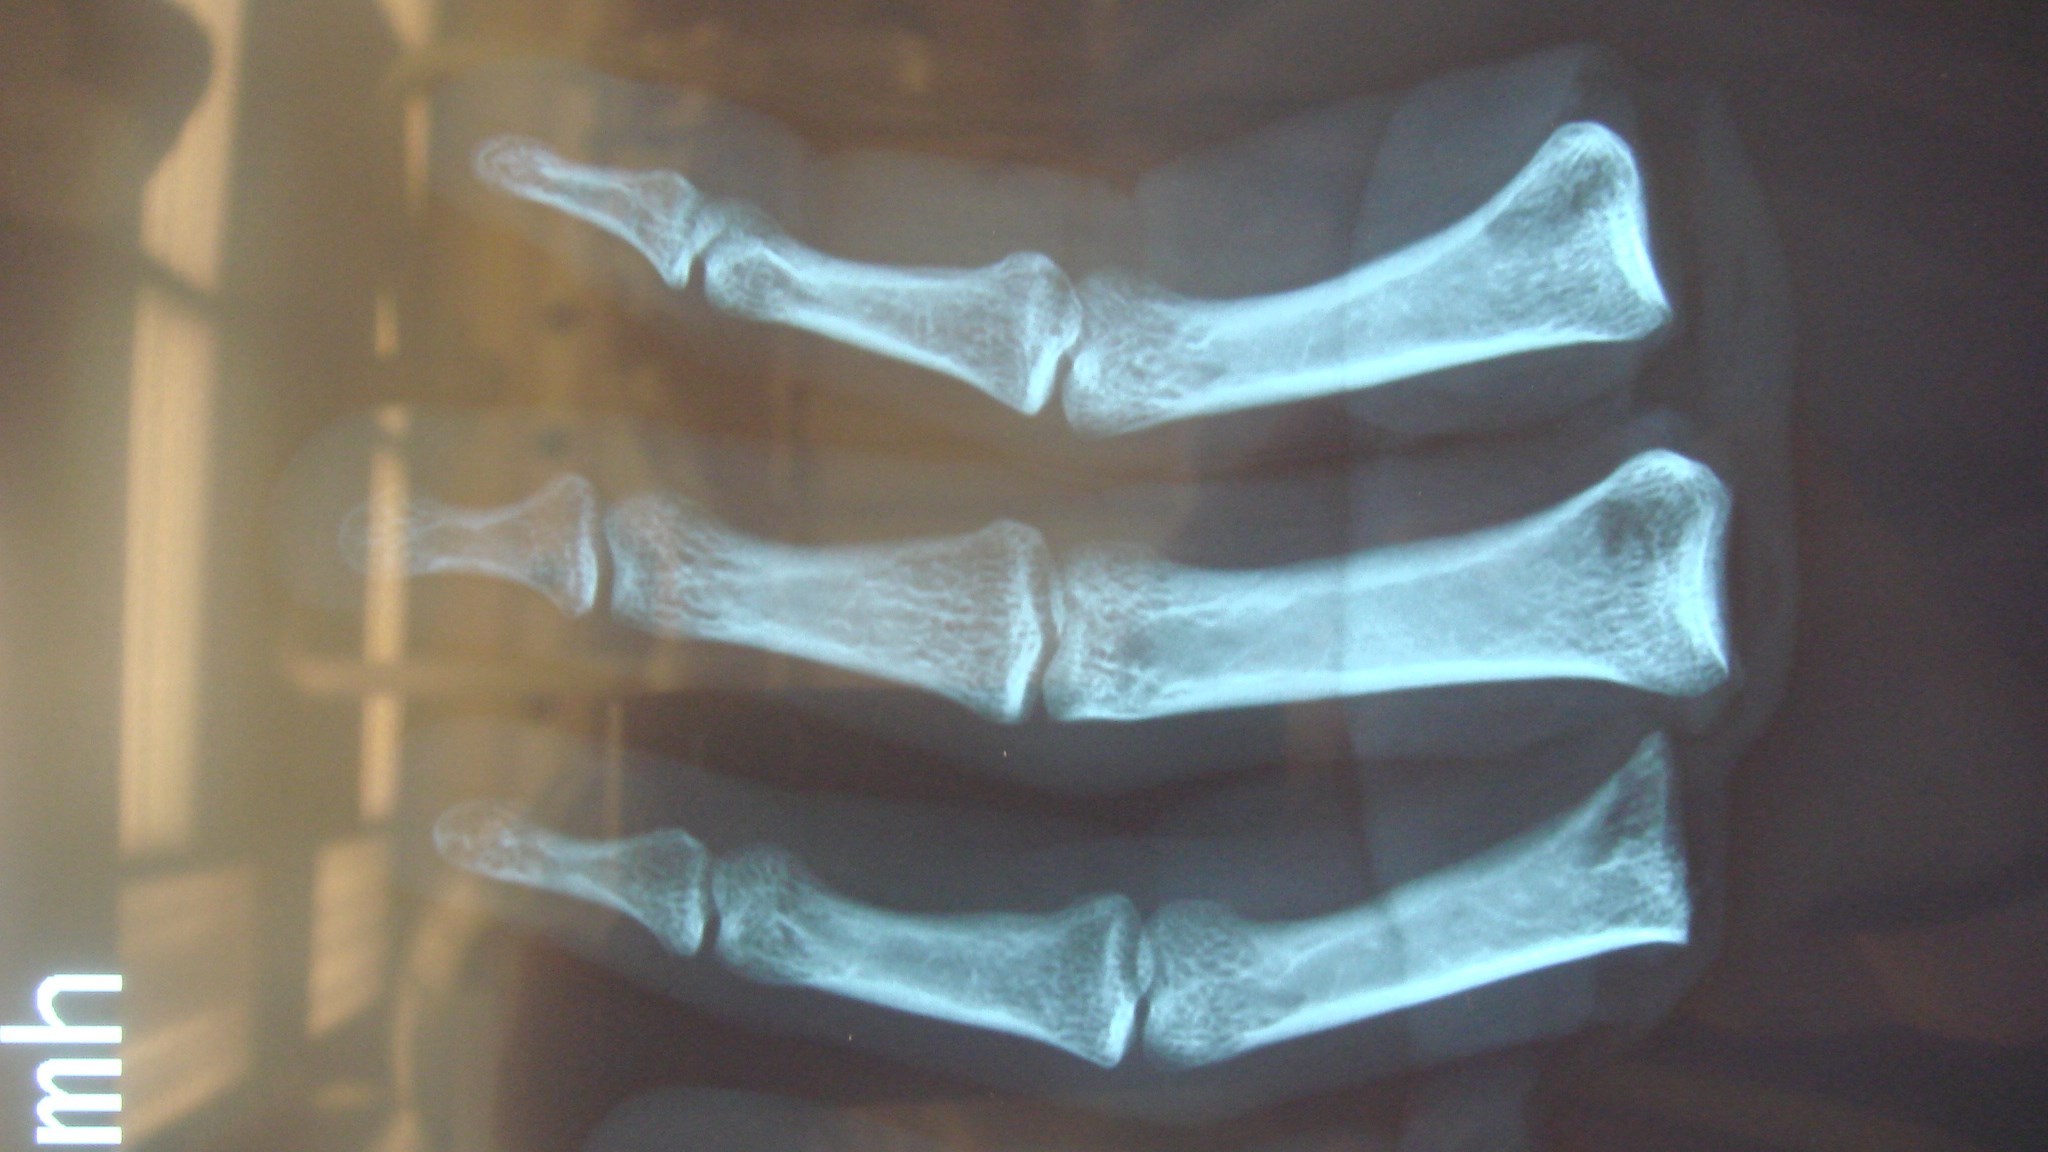

SR, CRP, leukocyt antal och andra prover ger också svag och sen indikation då den lokala infektionen endast ger svag allmän inflammation i kroppen. Diagnosen ställs istället via röntgenbildernas utseende. Ofta får röntgen undersökningen upprepas och man ser då suddigt avgränsade mörka områden som ibland kantas av en periostal reaktion.

Det tar vanligen 2-3 veckor för att röntgenförändringarna att utvecklas. En snabbare och tydligare diagnos kan man få genom MR eller Leukocyt scintigrafi men de ger dålig information efter trauma.